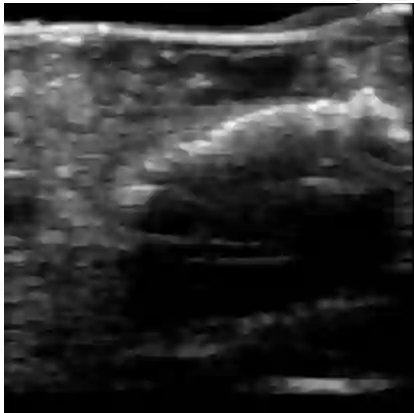

Chronic wounds including diabetic and arterial/venous insufficiency injuries have become a major burden for healthcare systems worldwide. Demographic changes suggest that wound care will play an even bigger role in the coming decades. Predicting and monitoring response to therapy in wound care is currently largely based on visual inspection with little information on the underlying tissue. Thus, there is an urgent unmet need for innovative approaches that facilitate personalized diagnostics and treatments at the point-of-care. It has been recently shown that ultrasound imaging can monitor response to therapy in wound care, but this work required onerous manual image annotations. In this study, we present initial results of a deep learning-based automatic segmentation of cross-sectional wound size in ultrasound images and identify requirements and challenges for future research on this application. Evaluation of the segmentation results underscores the potential of the proposed deep learning approach to complement non-invasive imaging with Dice scores of 0.34 (U-Net, FCN) and 0.27 (ResNet-U-Net) but also highlights the need for improving robustness further. We conclude that deep learning-supported analysis of non-invasive ultrasound images is a promising area of research to automatically extract cross-sectional wound size and depth information with potential value in monitoring response to therapy.